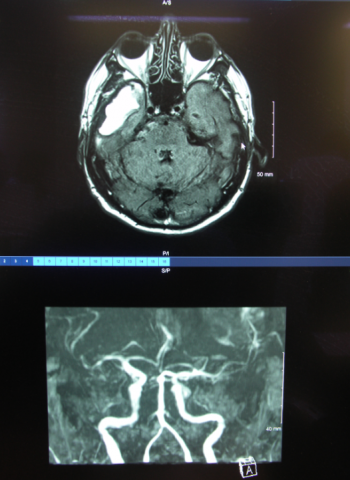

CREATION D’UNE USINV (Unité de Soins Intensifs Neuro-Vasculaire) A L’HOPITAL DE NEVERS

L’unité de soins intensifs neuro-vasculaire assure la prise en charge, à la phase initiale de leur maladie, des patients présentant une pathologie neuro-vasculaire aigue.